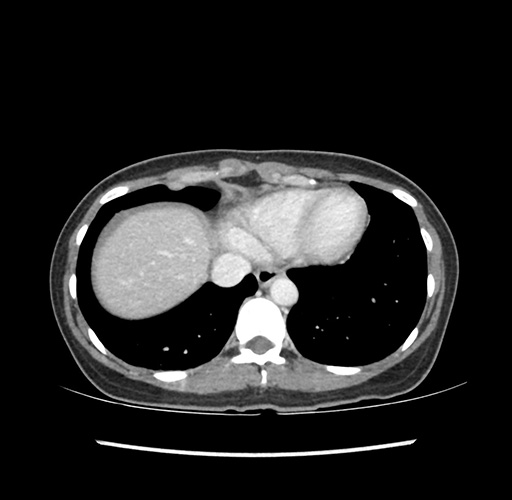

Imaging Analysis

Look through the patient's CT scan to identify any areas of concern for the necessary procedure.

Based on your CT findings, which issue(s) would give reason for "planned slowing down moment(s)" in this case?